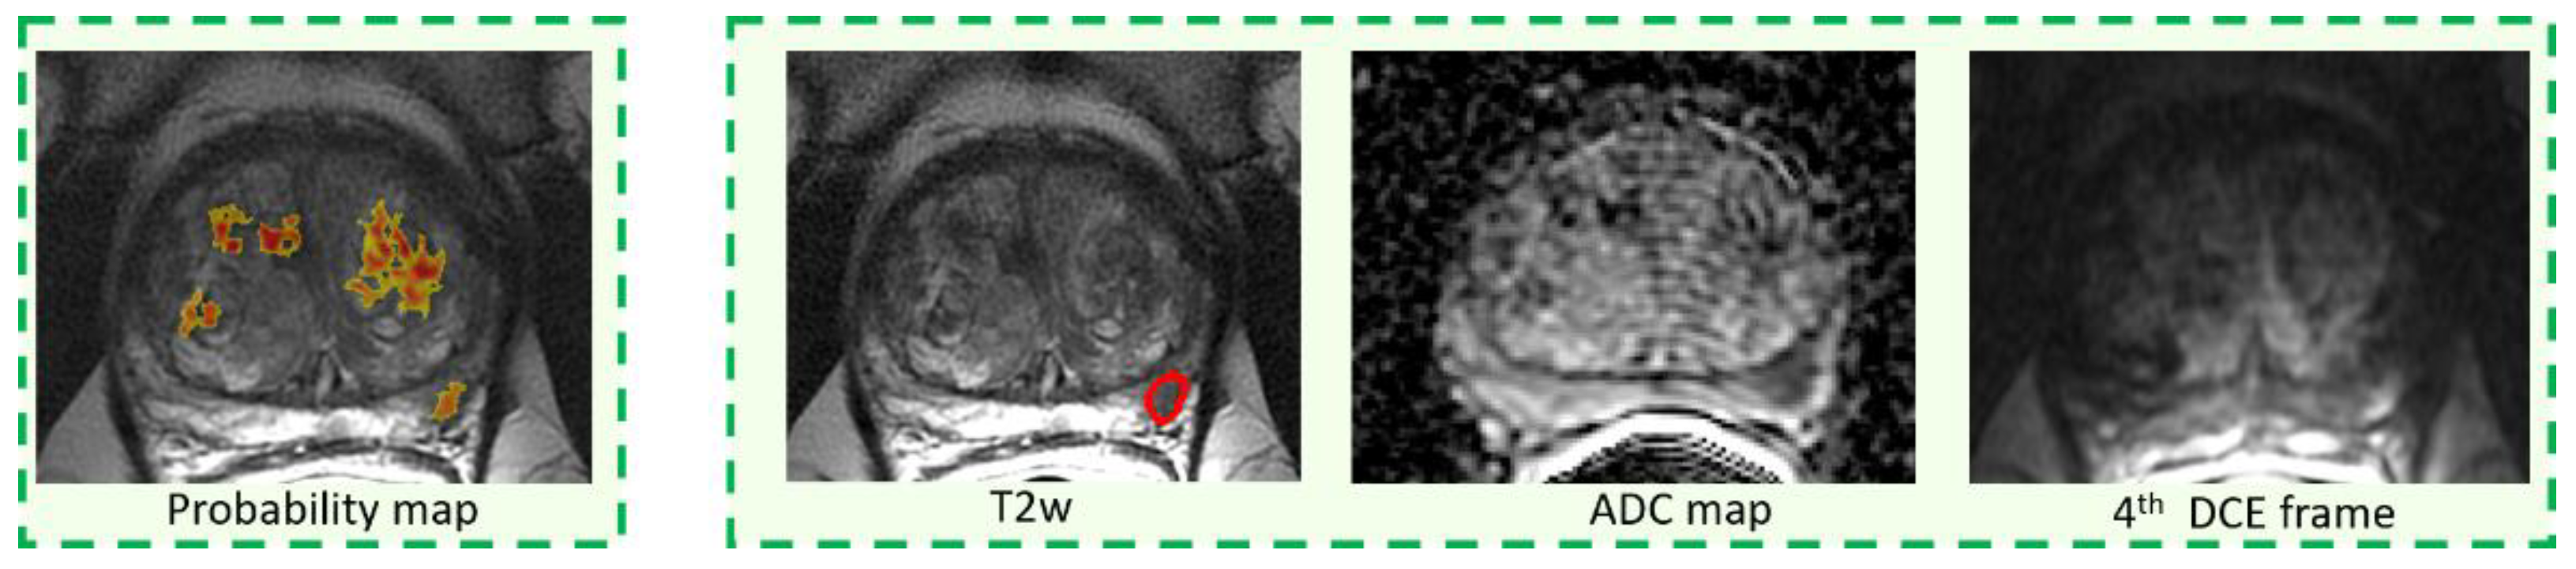

2.4. CAD System and Image Interpretation